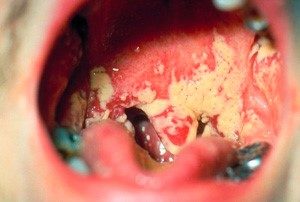

Течение кандидоза горла сопровождается в первую очередь наличием белого налёта в горле, на миндалинах и языке без повышения температуры. Для клинической картины лептотрихоза (кандидоза горла) характерны такие симптомы:

- Образование шипообразных выростов из лимфоидной ткани. Шипы в горле имеют белый или кремовый цвет и не вызывают дискомфорта.

- Наличие кандидоза полости рта. Появляются «заеды» в уголках рта, трещины на губах, гингивиты и стоматиты.

- Случайное выделение шипообразных пробок из миндалин.

Диагностика очень простая. Берут не мазок белого налёта, а часть шипообразной пробки из миндалин или корня языка. Под микроскопом обнаруживают нитеобразные бактерии Leptotrix Buccalis. Иногда они находятся вместе с грибками рода Candida.

Симптомы молочницы у детей При осмотре мама может увидеть небольшие белые пятнышки на губах, языке, деснах, в дальнейшем на их месте образуется белый творожистый налет. При попытке снять налет в домашних условиях могут образовываться маленькие кровоточащие ранки.